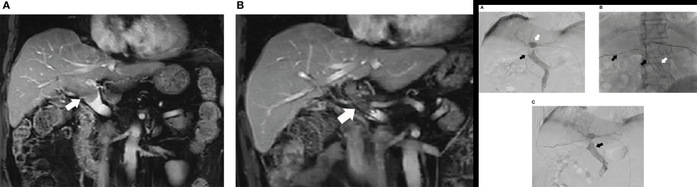

在转化治疗方面,项目聚焦不可切除患者“肿瘤学转化”与“残肝功能转化”两大核心目标,通过精细TACE提升缓解深度与持续性,增加获得根治性治疗机会的可能;并以门静脉栓塞术等为关键手段,在多学科协作框架下推动“评估—干预—再评估—决策”的流程化路径,使“从不可切除到可切除”具备可操作、可复制的临床闭环。

l 门静脉栓塞术后肝体积变化情况及肝切除图像